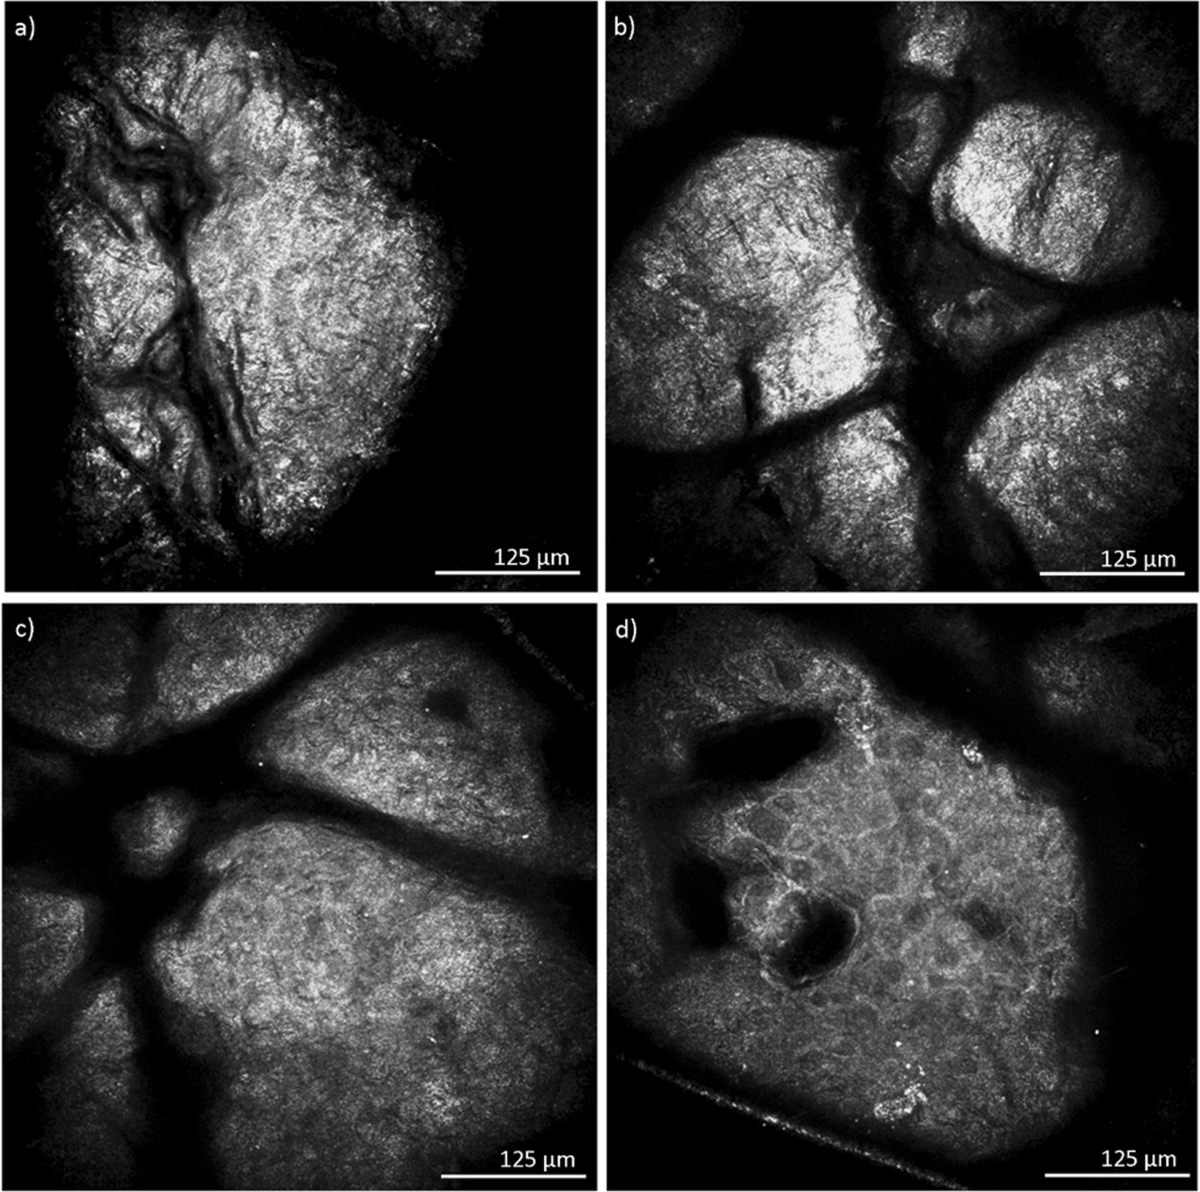

Advancement through epidermis using tape stripping technique and Reflectance Confocal Microscopy